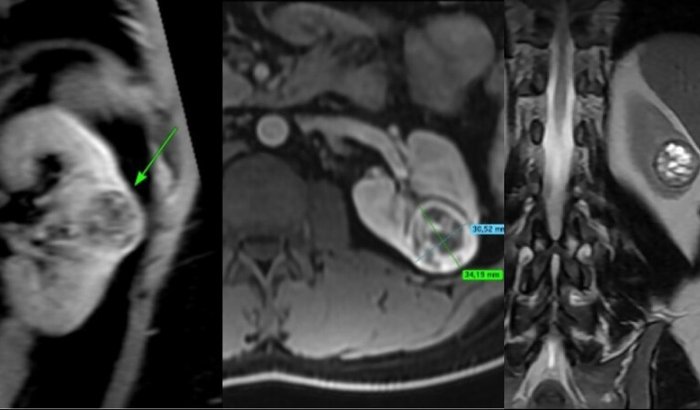

O tumor é agressivo, tem alta complexidade (RENAL score 9p) e está localizado muito próximo das vias urinárias, com risco de comprometer completamente meu rim.A única forma de me tratar com segurança e preservar ao máximo minha função renal é por meio de uma cirurgia robótica, um procedimento minimamente invasivo, de alta precisão. Mas infelizmente meu plano de saúde (SulAmérica) não cobre esse tipo de cirurgia.